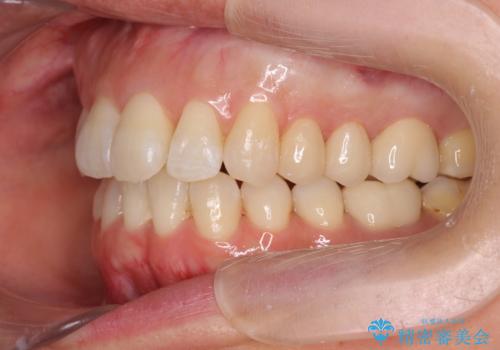

職業柄ワイヤー矯正ができない、マウスピース矯正で行う八重歯抜歯症例

- 「長年気になっている八重歯を矯正治療で治したい、ただし職業柄ワイヤー矯正は絶対にできないのでマウスピース矯正を希望。」

、と矯正治療を希望され来院されました。

通常は八重歯の抜去は行わず、小臼歯の抜去を行いワイヤー矯正を行いますが、八重歯を抜去することでマウスピースで現実的に達成できる機能的な歯並びを獲得できるよう治療計画を立案します。

治療に制約がある場合でも、現実的な治療ゴールを設定することで機能的・審美的な歯並びを手に入れることができました。